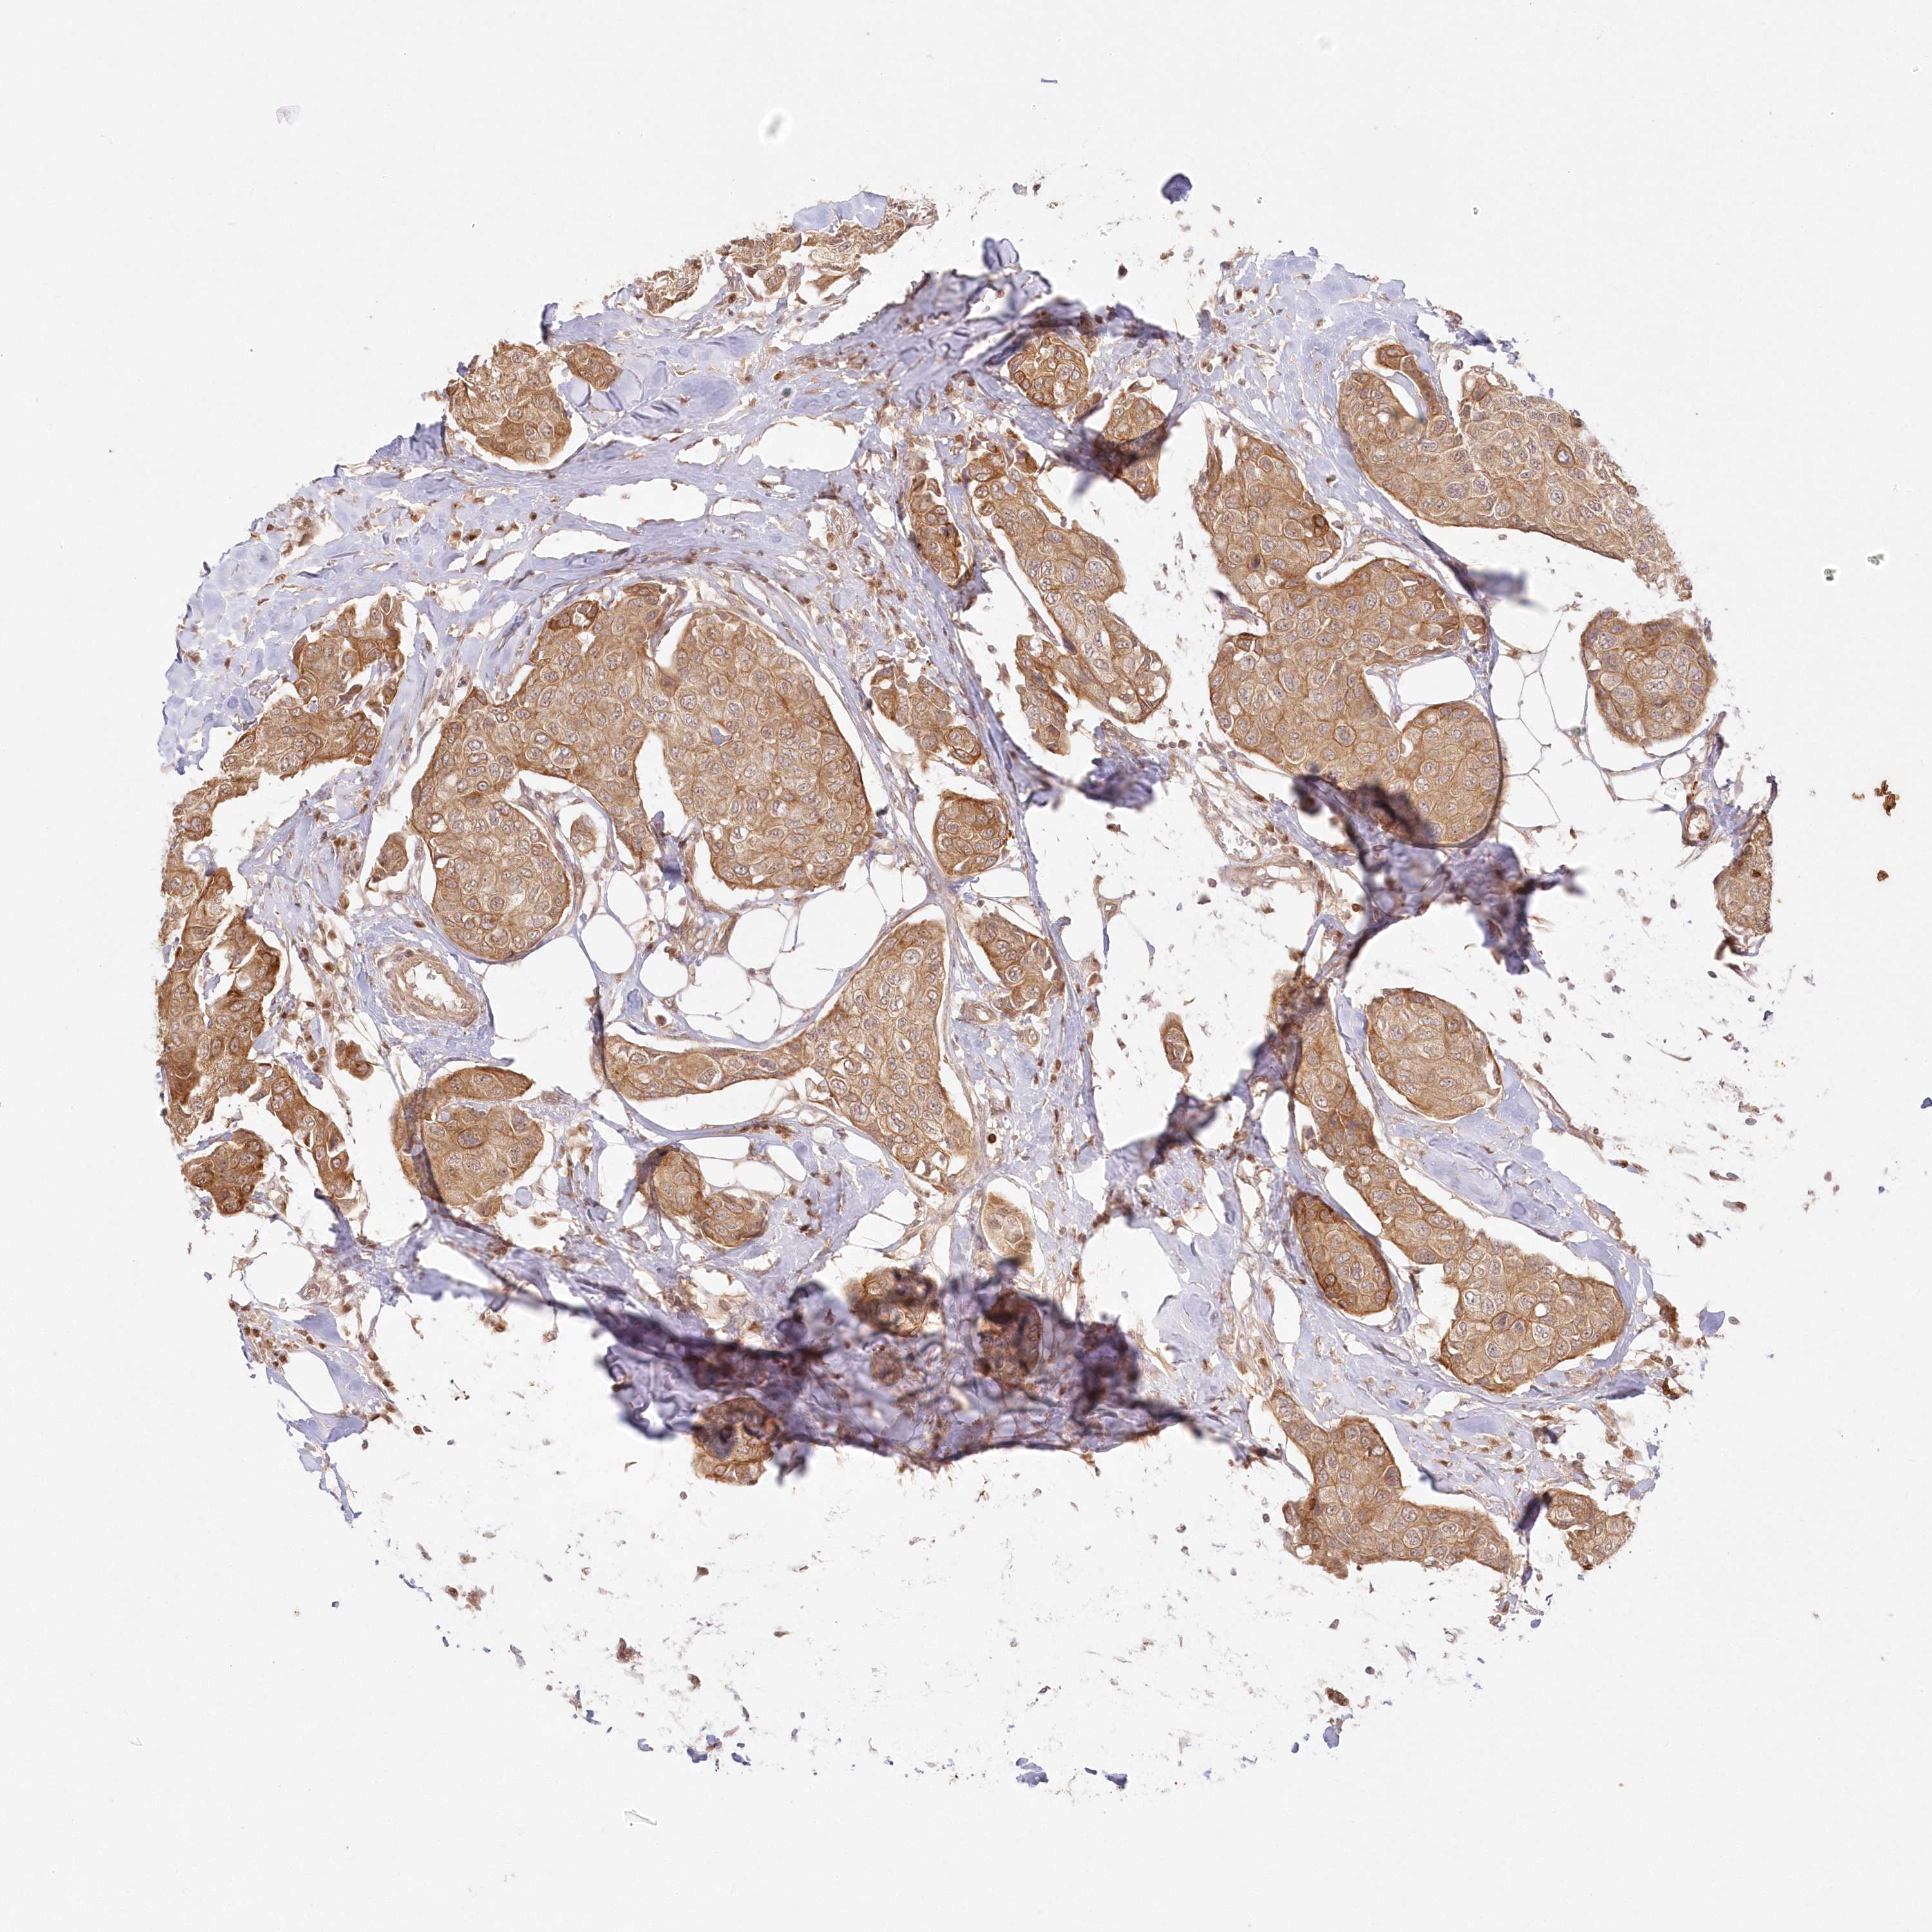

CANCER BREAST CANCER Show tissue menu

BRCA TCGA BRCA VALIDATION PROTEIN EXPRESSION

Breast cancer

Human cancer